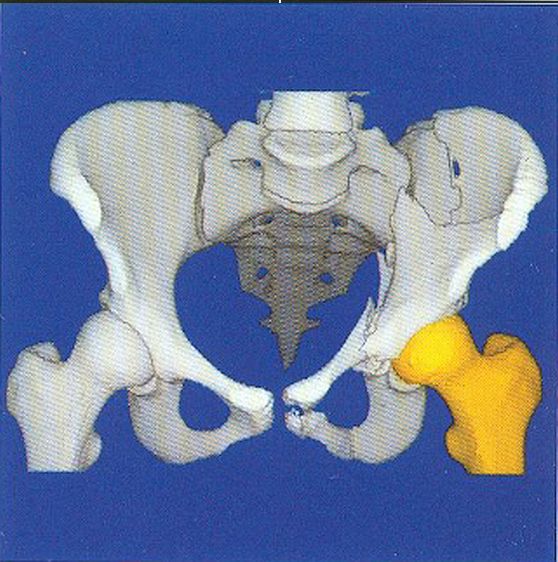

Here are typical examples of VoxelQ displays. These are mostly only windows, not the full screen which is more along the lines of the last block of AcQSim photos.

VoxelQ Multiplanar Reformatting (Axial, Saggital, Coronal, Curved)

VoxelQ Shaded Surface

VoxelQ Volume Rendering

VoxelQ Segmentation

VoxelQ Virtual Endoscopy